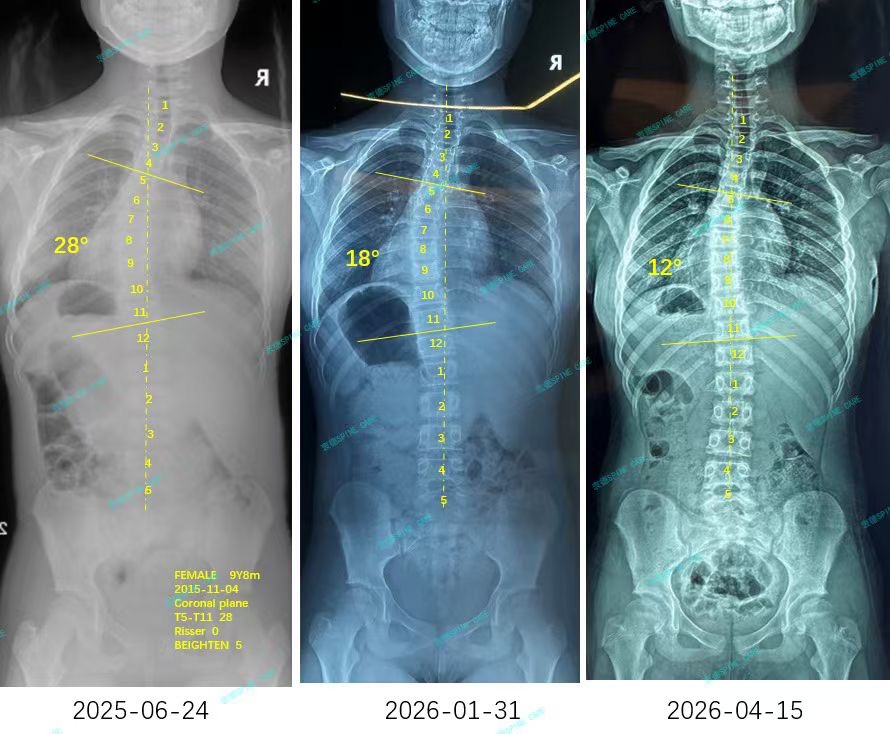

来自家长对衷德的评价(小瑜妈妈)

衷德脊柱,我们只关注侧弯保守治疗~

Zhongde Spine, bending no breaking ~